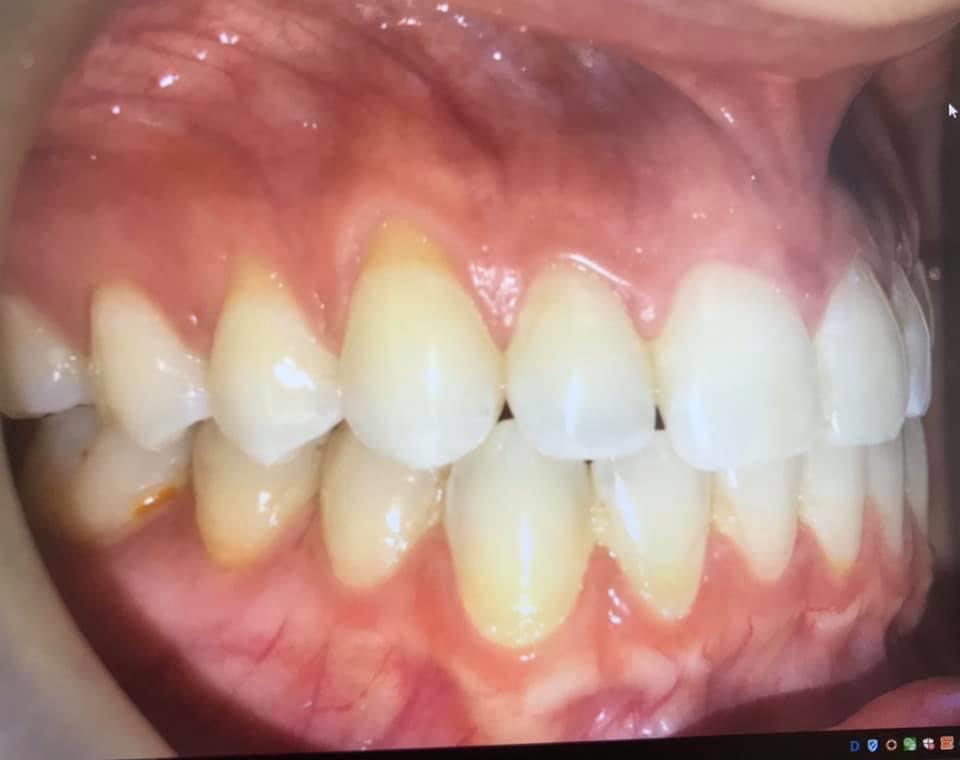

What is gum recession? Gum recession refers to the loss of gum tissue along the gumline. This can occur as a result of periodontal disease (gingivitis, periodontitis, advanced periodontitis), the natural aging process, or abrasive habits when it comes to brushing the teeth.

BEFORE AND AFTER PICTURES: